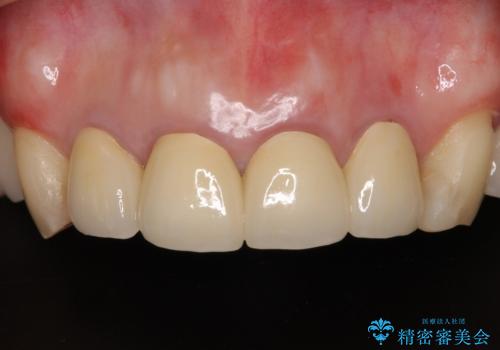

日頃の歯磨きをしっかりと行ってくださるので、新しい仮歯に変えてから速やかに歯肉の状態が改善されました。

歯肉からの出血がほとんどないため精度の良い型取りができ、非常に適合の良い補綴治療を行うことができました。